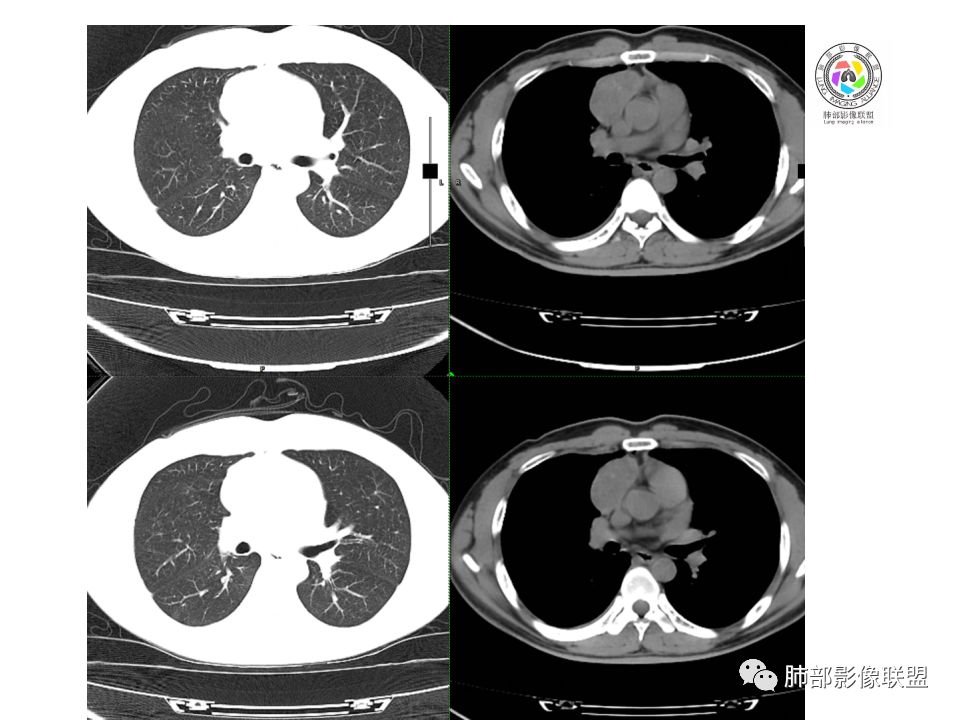

晨读:前纵隔占位,密度不均,沿着右侧纵膈延伸到肺门水平,周围支气管推移,大血管向内推移。临床有重症肌无力,考虑胸腺瘤可能,鉴别淋巴瘤。

右前纵膈肿块,偏一侧生长,形态欠规则,密度不均匀,其内可见小点状钙化,双肺多发小叶中心结节及钙化灶,右侧胸膜增厚(有陈旧性结核可能),青年男性(27岁),没有增强,考虑,1,前纵隔生殖细胞瘤2,精源细胞瘤

右前上纵隔占位,瘤肺交界面清楚,提示纵隔来源,其内有点状钙化,右侧胸腔积液,有临床症状,年龄轻,考虑生殖来源可能,胸腺瘤待排,请结合临床相关检查或CT增强进一步检查。

前纵隔占位,伴点状钙化;上腔静脉后移位。伴右胸膜局限性增厚,临床有重症肌无力,病人年轻,考虑胸腺瘤可能,鉴别生殖源性肿瘤。

右前纵隔占位,有分隔`低密度、点状钙化,边缘光滑,侵袭心包不明确,伴右胸少量积水,考虑恶性,生殖源性可能大,有视物不清,是否脑转移待查。建议HCG丶AFP检查。鉴别1:胸腺瘤、癌,30一40岁以下,少见,但有眼脸下垂,肌无力,待排除。2:淋巴瘤:侵袭性不强,有点状钙化,不支持。3:畸胎瘤:有低密度丶钙化,建议增强进一步明确。4:神经源性:一般后纵隔常见,不支持。5:LCD:症状少见,可以有树枝状钙化,浆细胞型可以有低密度,增强进一步明确

没有增强,好像两个病灶,上方三角形的像是胸腺增生。下方肿块,没有增强显得更难了,微钙化,轻度分叶,像有坏死低密度影,右侧少量胸水,胸膜受侵.,有视物模糊眼睑下垂。考虑胸腺瘤B1型及以上、B2型可能或生殖细胞瘤

前纵隔右区占位性病变,上区与胸腺延续,下区呈分叶状,尽管年龄<30还是首先考虑胸腺瘤,侵袭性可能性大(眼睑下垂不知是否有关)。鉴别主要是生殖细胞类肿瘤,主要是精原细胞瘤。另左肺上叶结核球,右侧胸腔积液,需除外结核性胸膜炎和转移

右前上纵膈肿块,内有点状钙化和少许小片状坏死,局部边界似欠清,右侧胸膜腔少量积液,年轻男性,小于30岁,有重症肌无力,虽然年龄偏轻,仍先考虑胸腺瘤,代排生殖源性肿瘤

晨读前纵隔肿块,偏右侧,密度不均,见点状钙化灶及分隔状低密度影。胸腺瘤>生殖细胞瘤>淋巴瘤

前纵膈占位,上腔静脉受推移,有分叶密度较均匀,结合临床考虑胸腺瘤,待排生殖细泡瘤.淋巴瘤

前中纵隔(胸腺癌区)不规则肿块,密度不均,有坏死区、点状钙化,边缘不会整肿块偏向右侧,向心包流注感,右胸腔少量积水。患者27岁,重症肌无力表现。

Forever:胸腺瘤

一、胸腺瘤基本知识

1.最常见的前纵隔肿瘤

2.发病年龄:40岁以上。30岁以下罕见

3.1/3出现重症肌无力,对诊断有提示意义

4.3-5%初诊时可发生远处转移

5.胸腺瘤病理标本上均伴有不同程度间隔存在

二、胸腺瘤CT诊断

1.位于前纵隔,心包旁,颈根部可见

2.常偏侧性生长,呈半球状

3.外缘光整或可见分叶

4.长径5-10cm,大于15cm罕见

5.大多数密度均匀,少数可出现小片状的低密度区

6.钙化0-20%,常为被膜或被膜下弧形钙化,实质内钙化见于A型以上

7.约30%CT增强后见低密度的线样纤维分隔;少数富血供

8.罕见纵隔淋巴结转移及远处血行转移

9.胸腺癌胸膜转移常见,对诊断有提示作用。